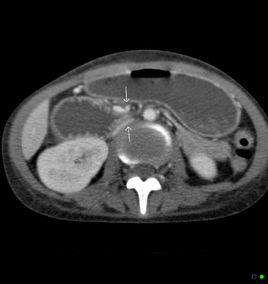

十二指腸橫段位於腹膜後,是消化道中最固定的部份。它從右至左橫行跨越第三腰椎和腹主動脈,十二指腸的遠端又被十二指腸懸韌帶(Trietz韌帶)所固定,其後方為腔靜脈、椎體和腹主動脈,其前方被腸系膜根部內的腸系膜上血管神經束所橫跨。腸系膜上動脈一般在第一腰椎水平處分出,與主動脈呈30~42°角。如果腸系膜上動脈與腹主動脈之間的角度變小,腸系膜上動脈即可將十二指腸橫部壓至椎體或腹主動脈上,造成腸腔狹窄和梗阻。

引起上述機械性梗阻常是多種因素的綜合結果,如腸系膜上動脈起始處呈一狹角,十二指腸懸韌帶過短而將十二指腸的遠端固定於較高的位置,腸系膜上動脈起源於腹主動脈的位置過低,在十二指腸跨越椎體處的前方有腸系膜上動脈的異常行走等等。此外,腰椎前凸畸形,十二指腸懸韌帶和腸系膜根部鄰近淋巴結炎性腫大,消瘦所致腸系膜和後腹膜脂肪減少,內臟下垂等等均可縮小脊椎與腸系膜上動脈近端部份之間的空隙,易使十二指腸遭受壓迫。